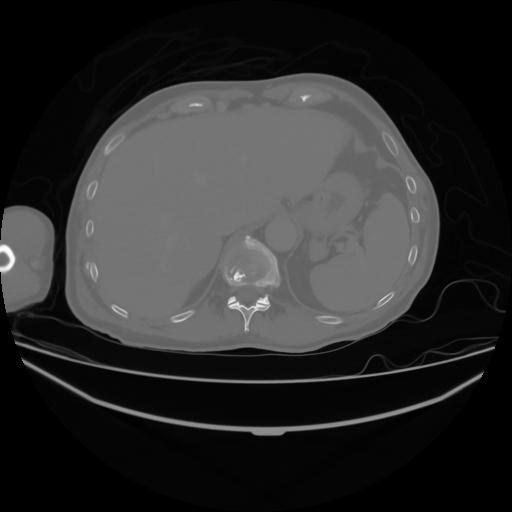

4 CUERPO,CE,Axial,3.0,CUERPO,,